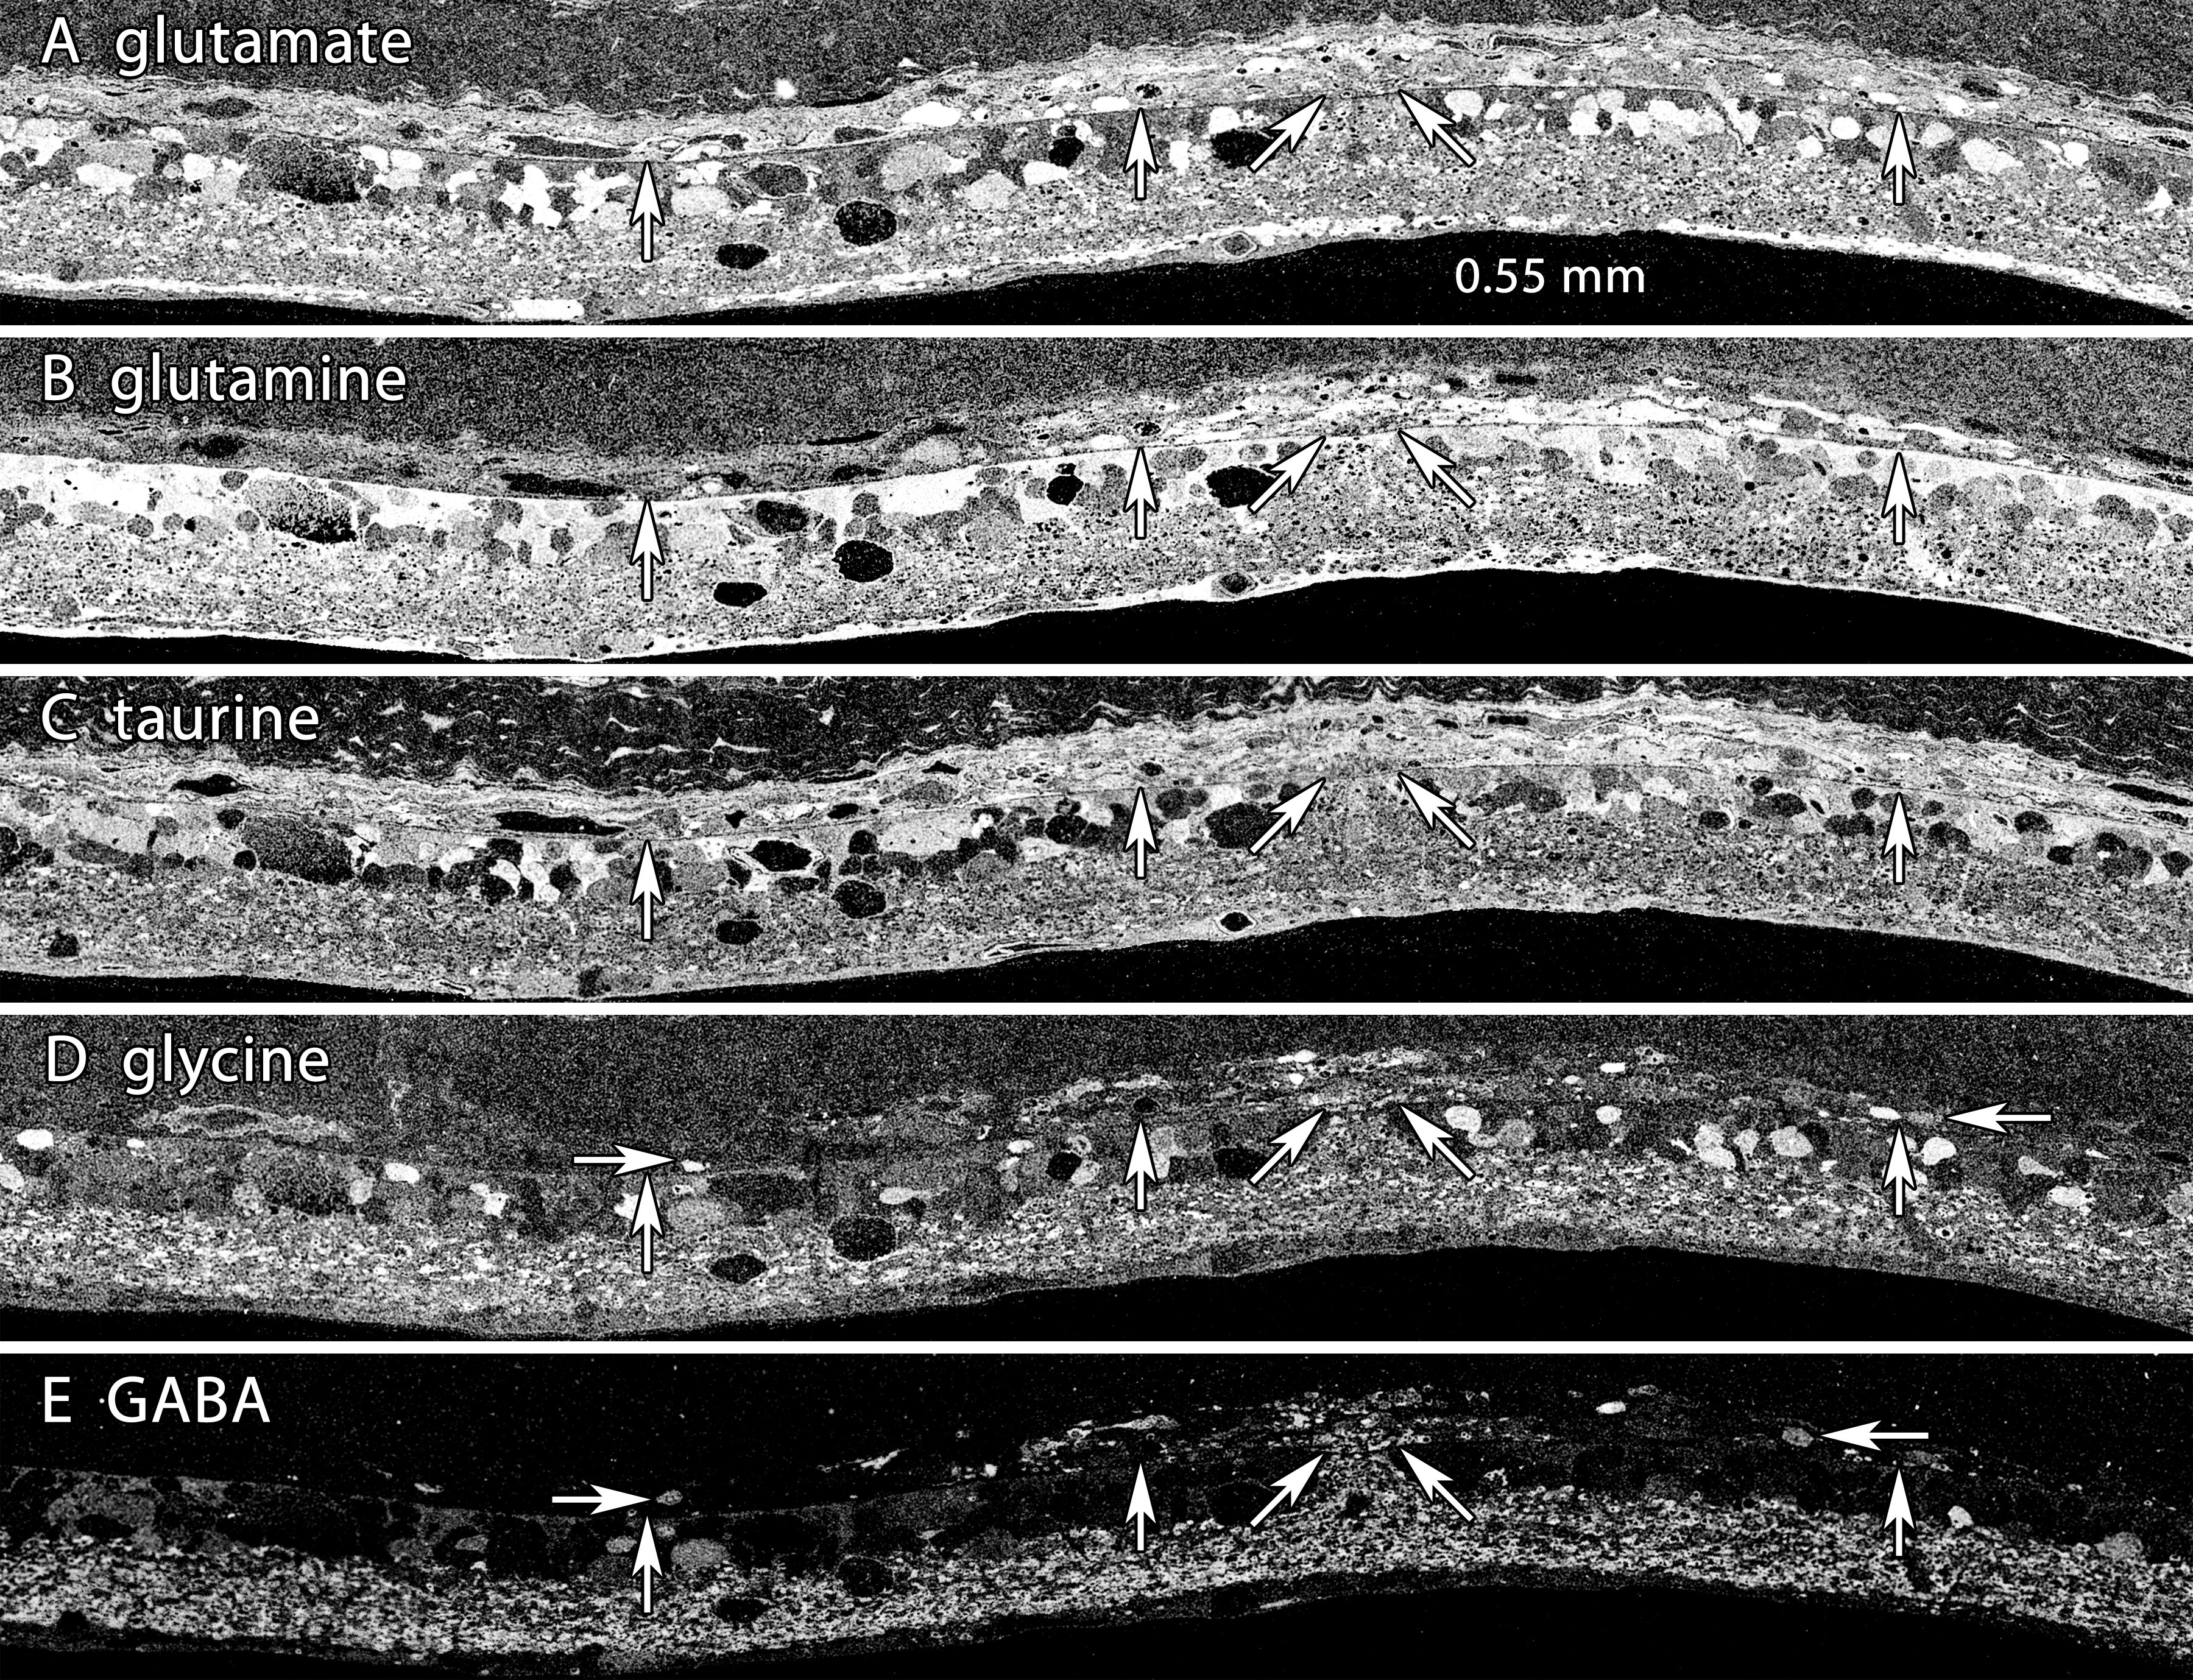

Figure 9. Eruption of neurites into the choroid. Visualization: Quantitative gray-scale images of molecular signals displayed as intensity.

Up arrows, remnant retina-choroid interface; horizontal arrows, neurons and neurites migrating in the choroid; angled arrows,

eruption site. Each panel is 0.550 mm wide. A: Glutamate signals do not readily reveal any interruption in the MC seal. B: Glutamine signals generally indicate that the MC seal is confluent, though subtle variations in signal strength between the

slanted arrows suggests an altered environment. C: Taurine signals do not readily reveal any interruption in the MC seal. D: Glycine signals indicate an eruption. Many glycinergic structures are located in the choroid distal to the arrows. E: γ-aminobutyric acid signals signals clearly indicate amacrine cell processes are entering the choroid. Sample metadata: SD

Rat, age at LX 60 d, animal #P240–3L-48–240, left eye, 48 h LX, harvested at 240 days pLX, bloc code 6693, slide code 3528.